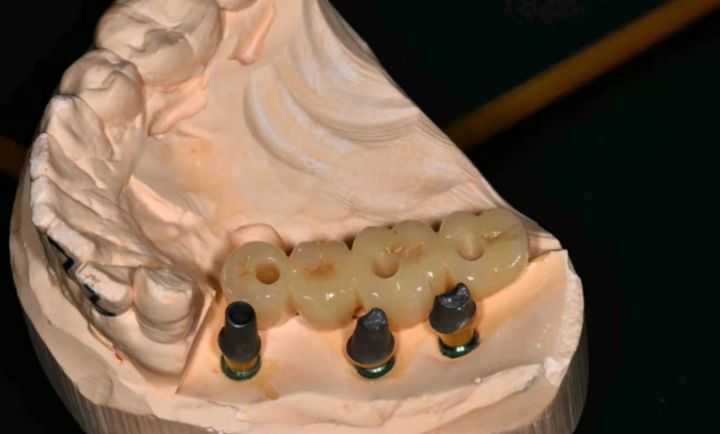

下面是一組利用種植導(dǎo)板做的種植案例:

圖:種植導(dǎo)板軟件果圖